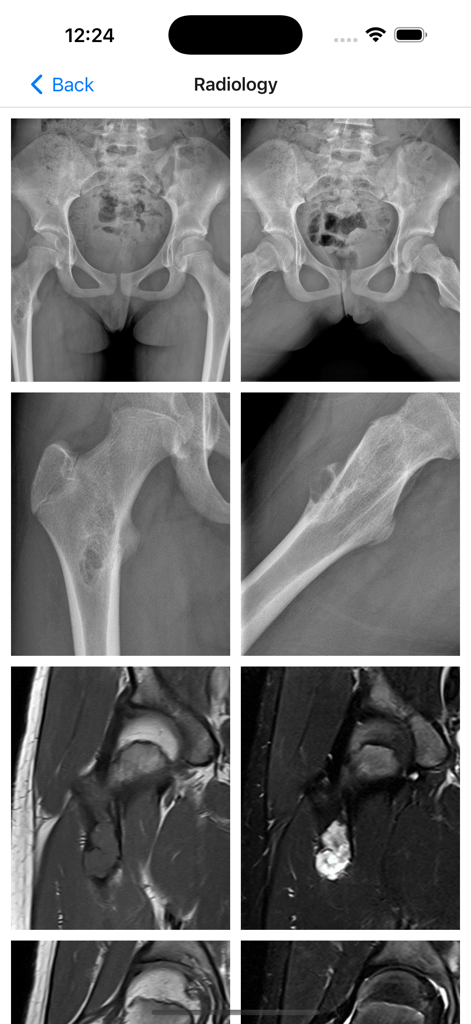

BoSTT - Radiology screen showing multiple X-ray and MRI scans for medical diagnosis

Radiology screen showing multiple X-ray and MRI scans for medical diagnosis